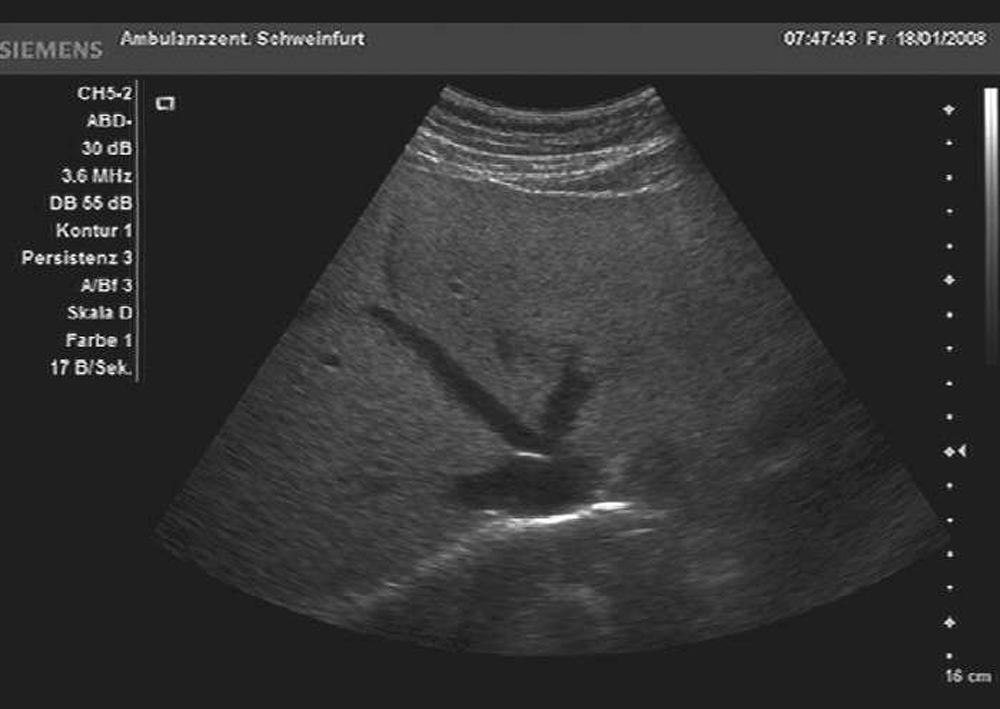

| Organe des Bauchraumes |

Dazu kommen neben dem üblichen schwarz-weiß Bild auch moderne Verfahren zum Einsatz wie Farbdopplersonographie und Kontrastmittelsonographie der Leber.